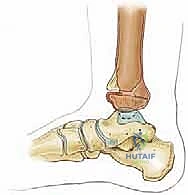

- كسر تيلوكس للمراهقين (Juvenile Tillaux Fracture): هو كسر من النوع الثالث لسالتر-هاريس، يحدث في الجزء الأمامي الوحشي (الخارجي) من قصبة الساق. يحدث عندما يكون الجزء الإنسي من لوح النمو قد أغلق، بينما الجزء الوحشي لا يزال مفتوحًا، فيقوم الرباط (AITFL) بانتزاع هذه القطعة.

- الكسر ثلاثي المستويات (Triplane Fracture): كسر شديد التعقيد يمر عبر ثلاثة مستويات مختلفة (سهمي، إكليلي، وعرضي). يظهر في الأشعة الأمامية ككسر سالتر-هاريس من النوع الثالث، وفي الأشعة الجانبية ككسر من النوع الثاني. يتطلب هذا الكسر دائمًا فحصًا مقطعيًا (CT Scan) لتقييمه بشكل صحيح.